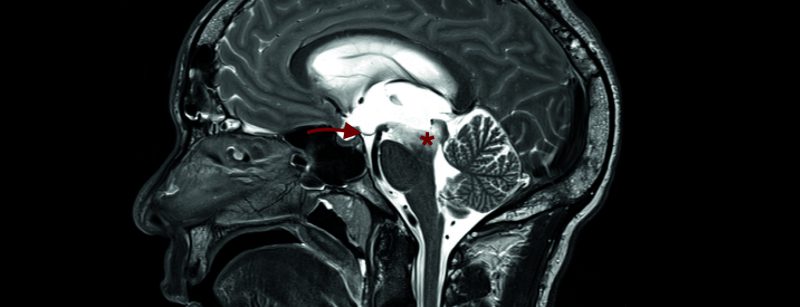

Hydrocephalus occlusus als Erstmanifestation einer HIV-Infektion

Primärkonsultation: Der 42-jährige Patient stellte sich Anfang Februar 2016 notfallmässig in unserer Klinik wegen progredienter Gangunsicherheit, Verlangsamung, kognitiven Einschränkungen und nächtlicher Inkontinenz vor. Anamnestisch bestanden keine Vorerkrankungen, insbesondere keine immunsuppressive...…